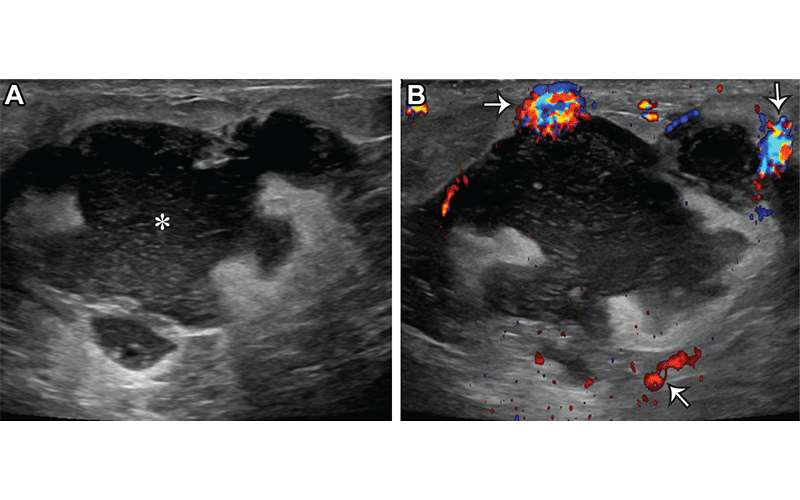

Acute puerperal abscess in a 26-year-old lactating woman who presented with skin erythema, warmth, and pain. (A) Gray-scale US image shows an irregular complicated fluid collection (*). (B) Color Doppler US image shows hyperemia surrounding the fluid collection (arrows). US-guided aspiration yielded purulent fluid, and cultures grew methicillin-resistant Staphylococcus aureus (MRSA). https://pubs.rsna.org/doi/10.1148/rg.230014 ©RSNA 2023